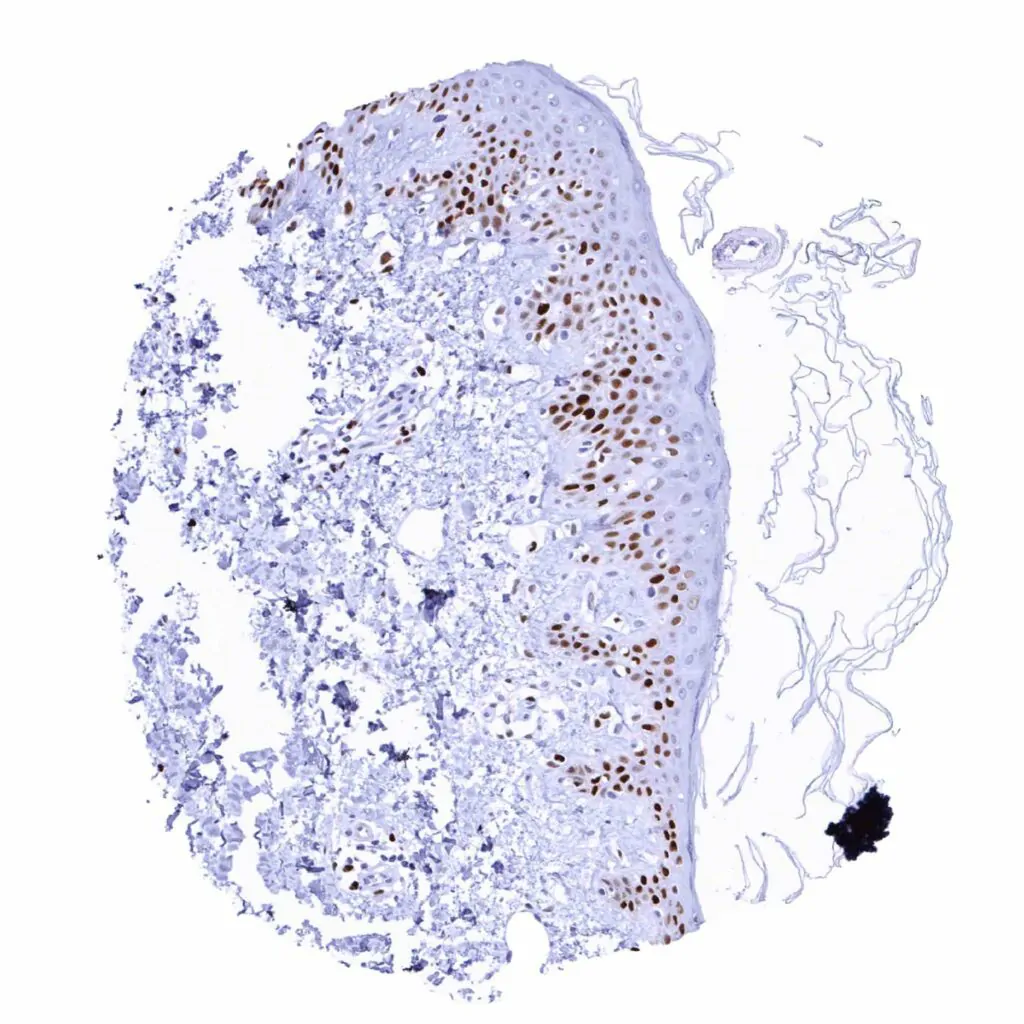

Skin – Suprabasal and basal cell layers (weaker) of the squamous epithelium show a distinct MCM2 positivity